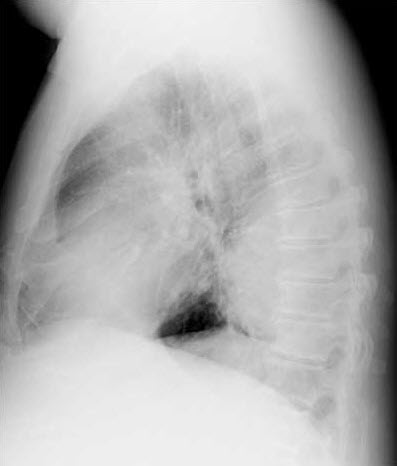

The posteroanterior chest radiograph suggests a rounded retrocardiac density in the left hemithorax (Figure 1). This is confirmed by the lateral view, which shows a large posterior lobulated shadow (Figure 2). The differential diagnosis at this point includes loculated pleural effusion, lung abscess without an air-fluid level, and thoracic empyema with or without an underlying malignancy. A chest CT scan delineates a 9 3 8-cm rounded density (Figure 3). The difference in homogeneity suggests a walled-off fluid collection with no evidence of air.